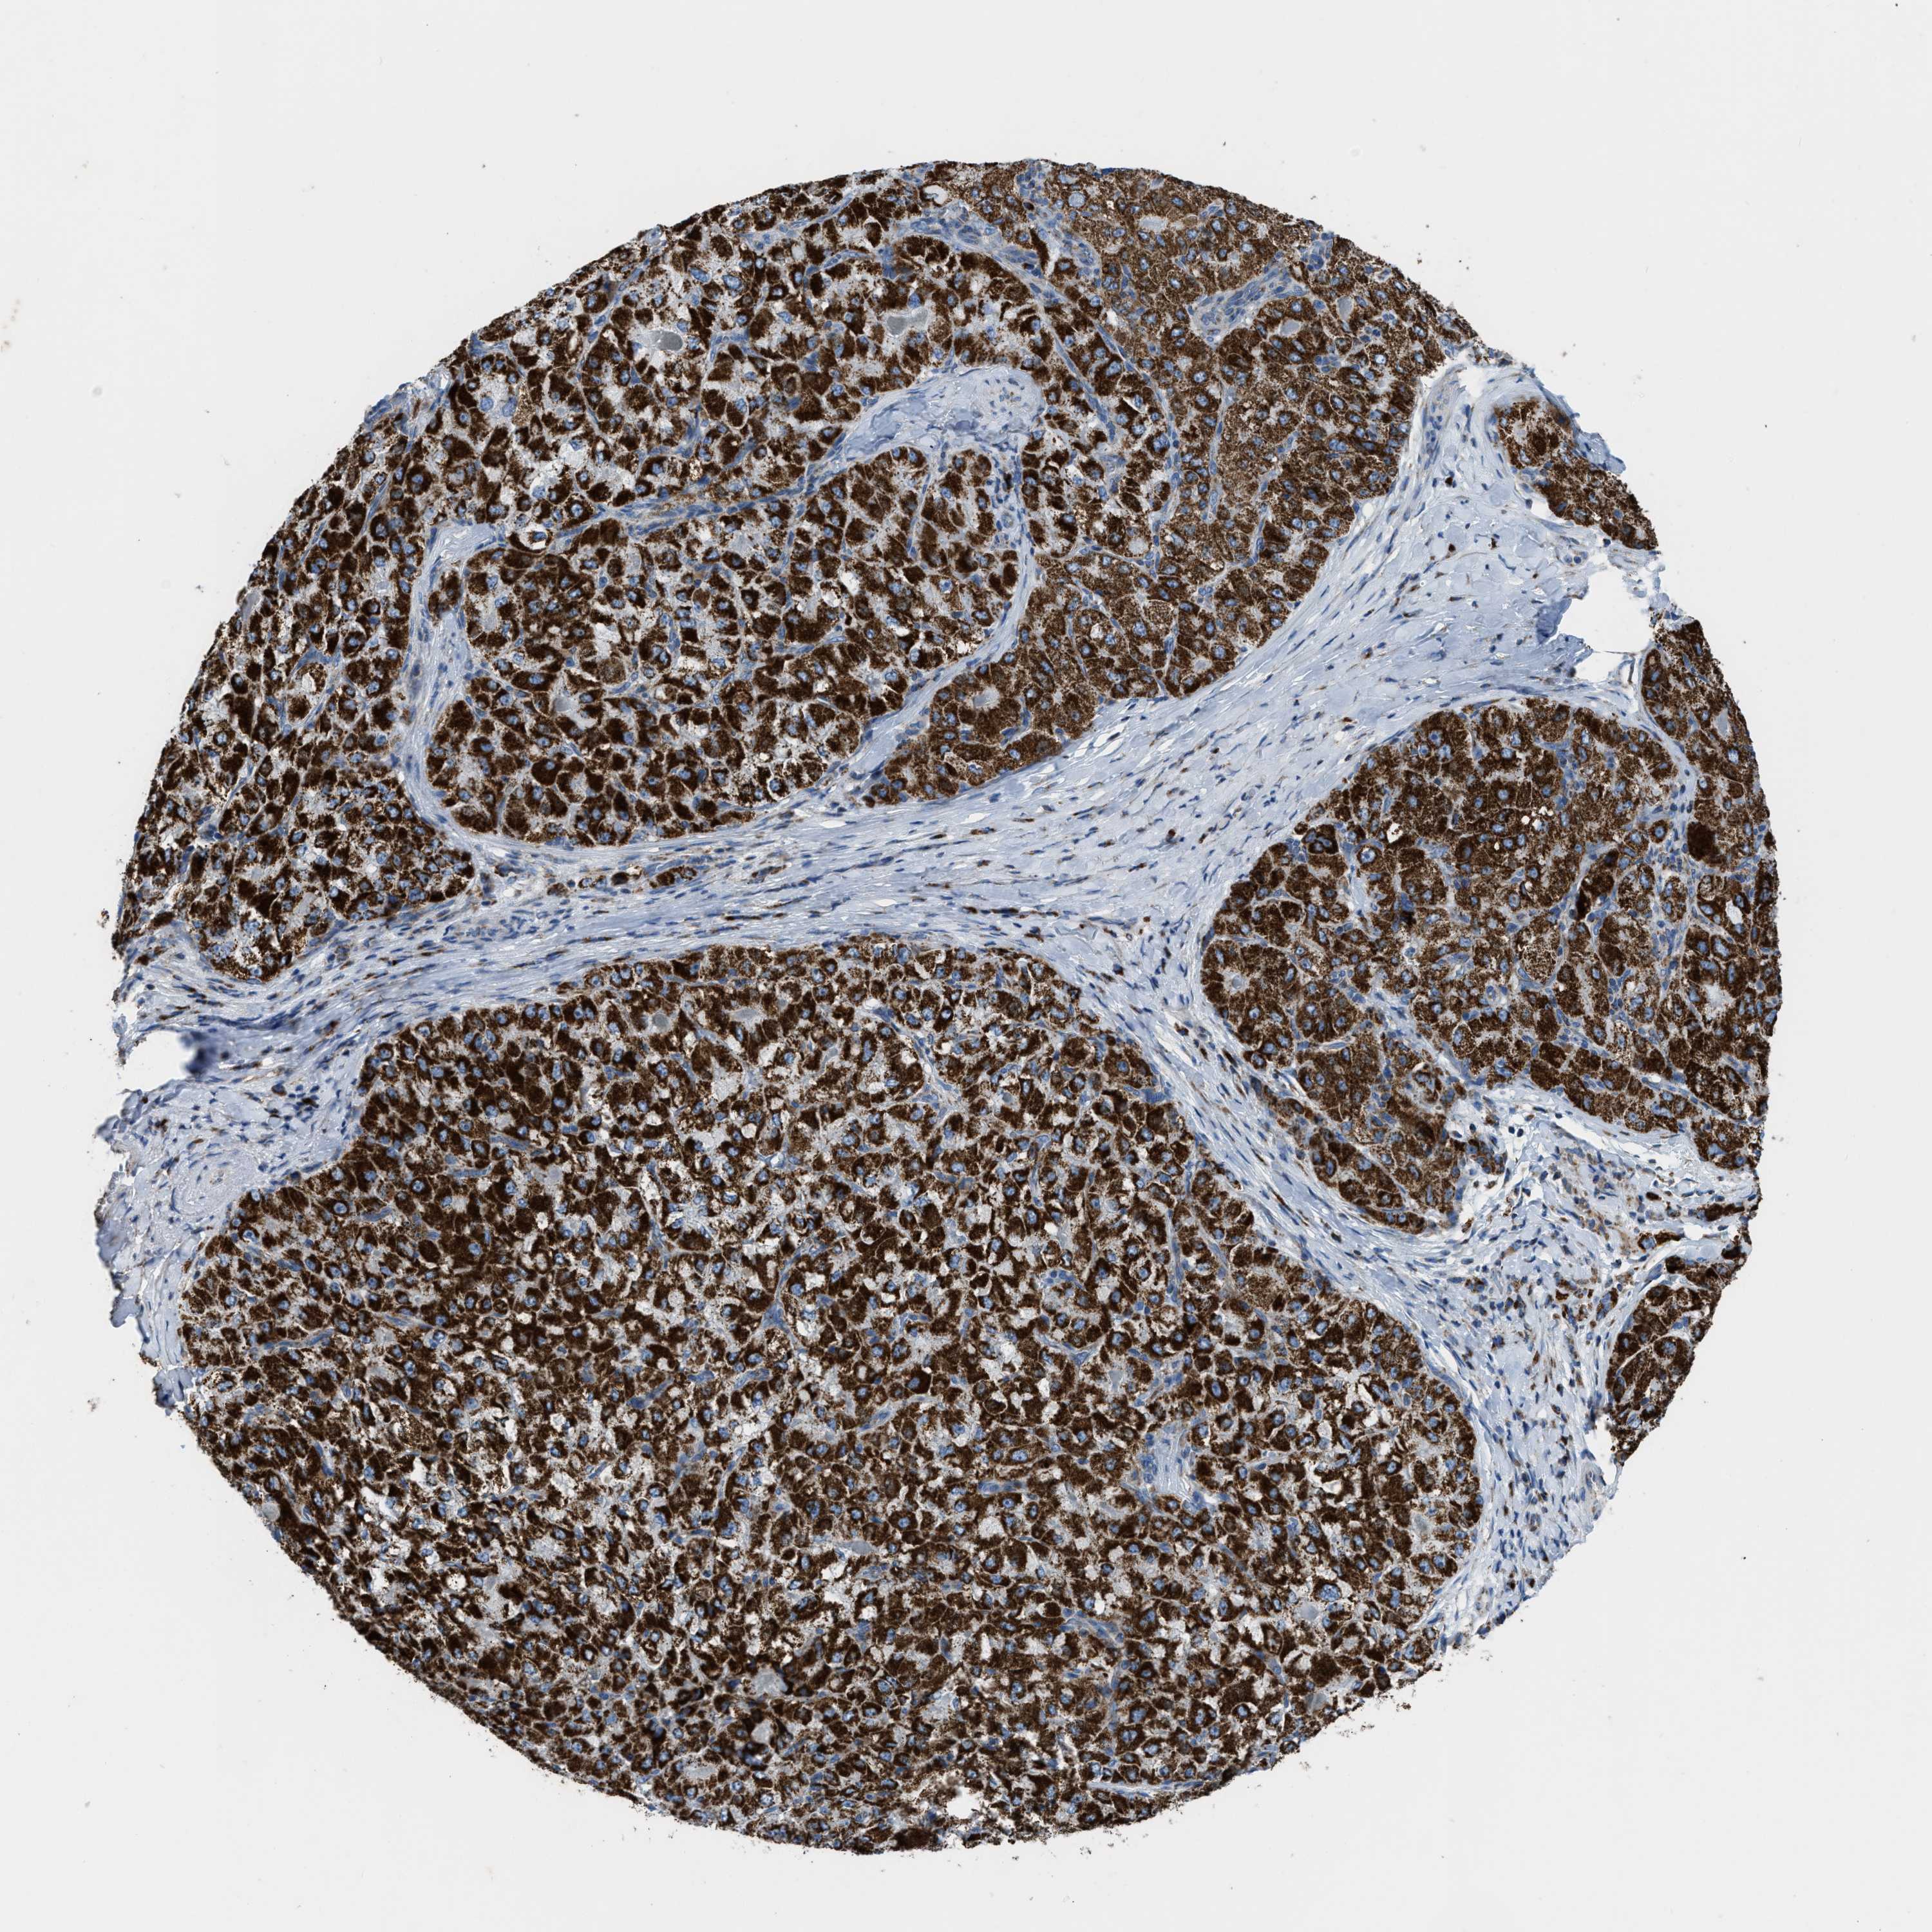

LIVER CANCER - Protein expressioni

A mouse-over function shows sample information and annotation data. Click on an image to view it in a full screen mode. Samples can be filtered based on level of antibody staining by selecting one or several of the following categories: high, medium, low and not detected. The assay and annotation is described here.

Note that samples used for immunohistochemistry by the Human Protein Atlas do not correspond to samples in the TCGA dataset.

Antibody stainingi

Antibody staining in the annotated cell types in the current human tissue is reported as not detected, low, medium, or high, based on conventional immunohistochemistry profiling in selected tissues. This score is based on the combination of the staining intensity and fraction of stained cells.

Each image is clickable and will lead to virtual microscopy that enables deeper exploration of all samples and also displays staining intensity scores, fraction scores and subcellular localization as well as patient and tissue information for each sample.

Antibody HPA018910

Antibody HPA018921

Antibody HPA018923

Staining

High

Medium

Low

Not detected

Intensity

Strong

Moderate

Weak

Negative

Quantity

>75%

75%-25%

<25%

None

Location

Nuclear

Cytoplasmic/membranous

Cytoplasmic/membranous,nuclear

Cholangiocarcinoma

Carcinoma, Hepatocellular, NOS